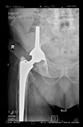

The guiding wire was inserted and controlled with fluoroscopy flashes (Figure 4). The drilling and reaming were carried out in accordance with the recommendations:

Figure 4.

The biocompatible aiming device after insertion of the guiding wire.

In all the cases operated with the above-described targeting procedure, the stems of the cups remained between the cortical bone surfaces without perforation of the linea terminalis, as shown by postoperative radiographs. There were no complicated surgical situations. In 16 cases, the wound healings were uneventful, and the hips were able to bear weight again after postoperative rehabilitation.